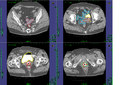

Project Title: Contouring of Anatomy Structures like Tumor, Bladder, Rectum and Sigmoid for Gynecological Brachytherapy

This project aims to support the time consuming manual slice by slice segmentation process of contouring the anatomy structures for Gynecological Brachytherapy. Therefore (semi-)automated segmentation tools under the medical platform 3D Slicer are used to extract the anatomy structures like tumor, bladder, rectum and sigmoid. Furthermore, we want to evaluate the segmentation results achieved with the tools from 3D Slicer by using the manual segmentations.